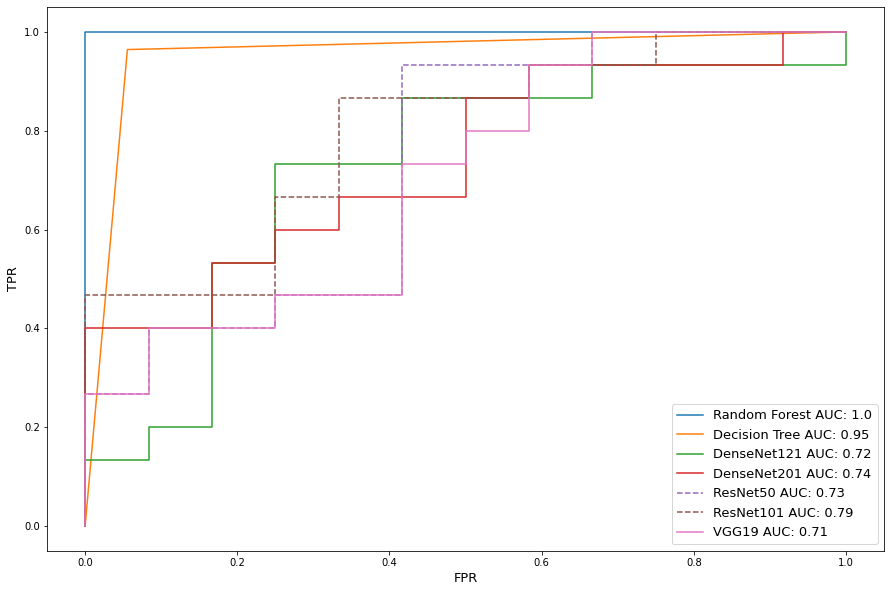

Table 4 shows the classification performance for the augmented data. We see the addition of data allows near perfect score improvement for the deep learning models. However, the increase in sample size decreased overall conventional machine learning algorithm accuracy due to a higher possibility for false predictions. This phenomenon is also reflected in Figure 6 as deep learning reached AUC scores nearing 1.0, while the Decision Tree AUC score dropped 0.05 from Figure 5.

3.2.2 Data Augmentation

In this section, we repeat the previous tests using data augmentation. In accordance with section 3.1.3, Table 6 shows data augmentation of CT scans does improve deep learning accuracy. Random forest performance is on par with ResNet101, showing the feature pool for 266x340 images could be more representative of the class boundaries when compared to localized 128x128 image slices. Mean accuracy by model, however, is lower by 0.0148%, equating to 15 additional misdiagnoses per 1000 scan classifications, confirming a larger feature pool is more difficult to learn efficiently. Perfect untampered precision and tampered recall scores, and lower untampered recall and tampered precision on SVM, DenseNet201, and ResNet50 indicate overcompensation on tampered predictions while correctly classifying 92% of untampered scans. Given perfect model accuracy is non-viable, this is the preferred scenario considering loss of life is more concerning than expense of resources. AUC scores in Figure 9 indicate excellent performance.